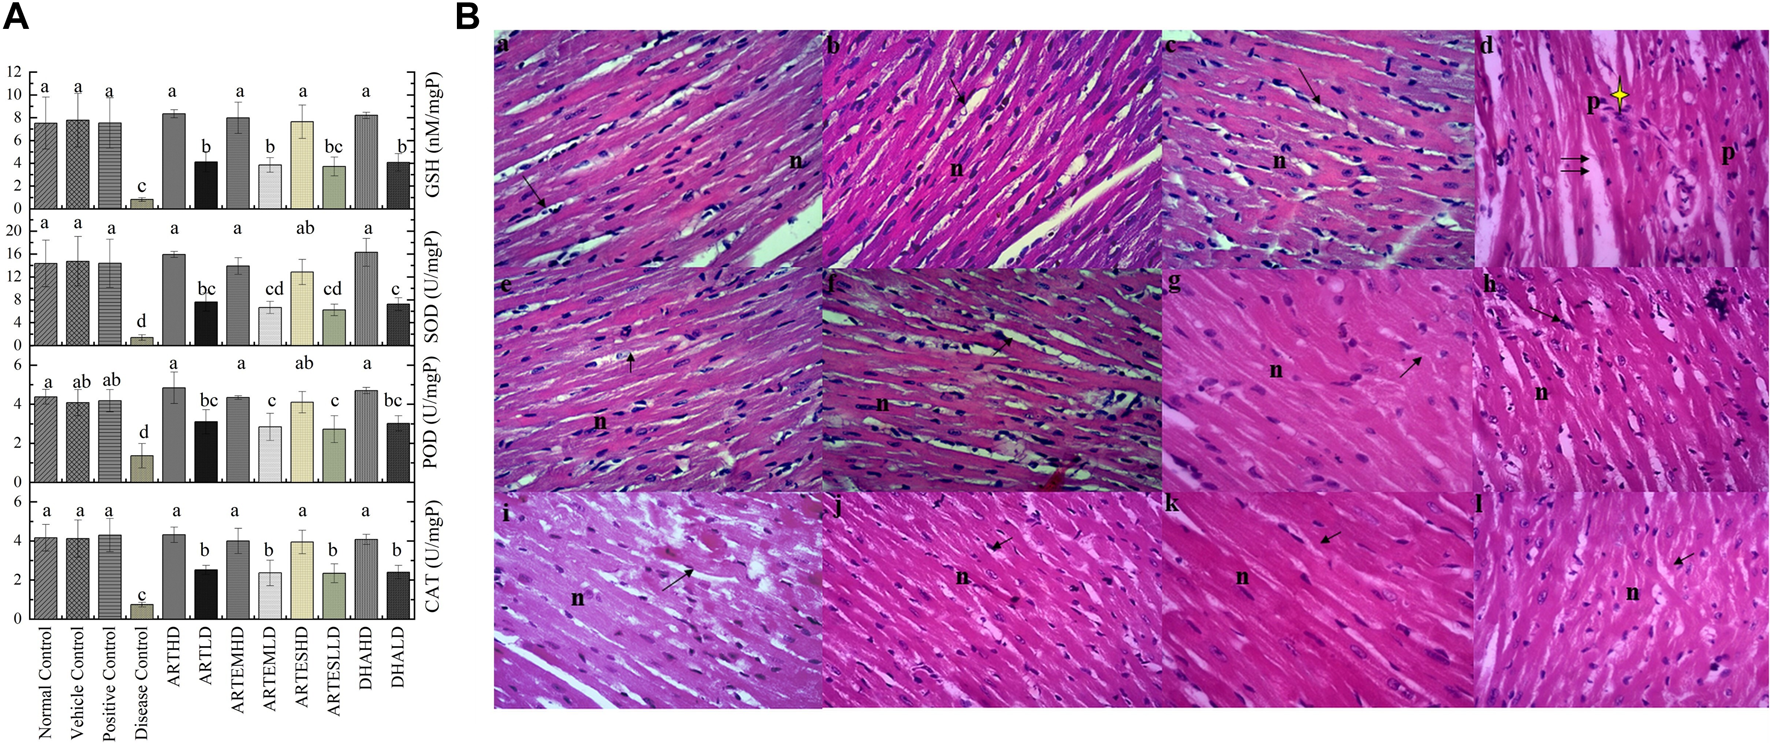

3.6.2 Effects on endogenous antioxidants

The effects of artemisinic compounds on cardiac enzymatic levels are presented in Figure 4A. Compared to the normal control, the disease control significantly (p < 0.05) decreased the activity levels of CAT, POD, and SOD to 0.74 ± 0.11 U/mg, 1.36 ± 0.62 U/mg, and 1.41 ± 0.5 U/mg protein, respectively. Depleted GSH content was also observed in the disease control at 0.81 ± 0.2 nM/mg protein. The AC-treated groups exhibited a significant (p < 0.05) and dose-dependent rise in antioxidant levels with the HD of ART maximally attenuating the activity levels of CAT, POD, and SOD to 4.32 ± 0.39 U/mg, 4.84 ± 0.8 U/mg, and 15.91 ± 0.5 U/mg protein. Additionally, the GSH content was also restored to 8.34 ± 0.4 nM/mg protein in the ARTHD-treated group. The vehicle control did not exhibit any toxicity.

FIGURE 4

(A) Effects of artemisinic compounds on endogenous antioxidant levels in cardiac tissues. The results are presented as mean ± SD (n = 5). Means with different superscript (a–d) letters are significantly different from one another, according to Tukey’s multiple comparison test at p < 0.05. (B) Hematoxylin and eosin (H&E) stained cardiac cross sections: (a) normal control, (b) vehicle control, (c) positive control, (d) disease control, (e) ARTHD, (f) ARTLD, (g) ARTEMHD, (h) ARTEMLD, (i) ARTESHD, (j) ARTESLD, (k) DHAHD, and (l) DHALD. The double arrows point to increased spacing between cells, n shows central vesicular nuclei, the single arrows point to striated eosinophilic sarcoplasm, and the yellow star identifies periventricular infiltration of inflammatory cells. HD, high dose; LD, low dose; ART, artemisinin; ARTEM, artemether; ARTES, artesunate; DHA, dihydroartemisinin.

3.6.4 Effects on cardiac histoarchitecture

The cardiac histology (Figure 4B) of the normal control exhibited a branched and striated myofibrillar structure. The disease control exhibited severe cardiotoxicity with significant pathological changes, including inflammation, vacuolization, eosinophilic infiltration in the cytoplasm, hyaline necrosis, and loss of proper striations compared to the normal control. Artemisinic compounds neutralized the CCl4-induced distortion. Herein, cardiac sections from the groups treated with HDs exhibited normal histoarchitecture with branched and striated myofibrils. Mild vacuolization can be observed in LD-treated groups.